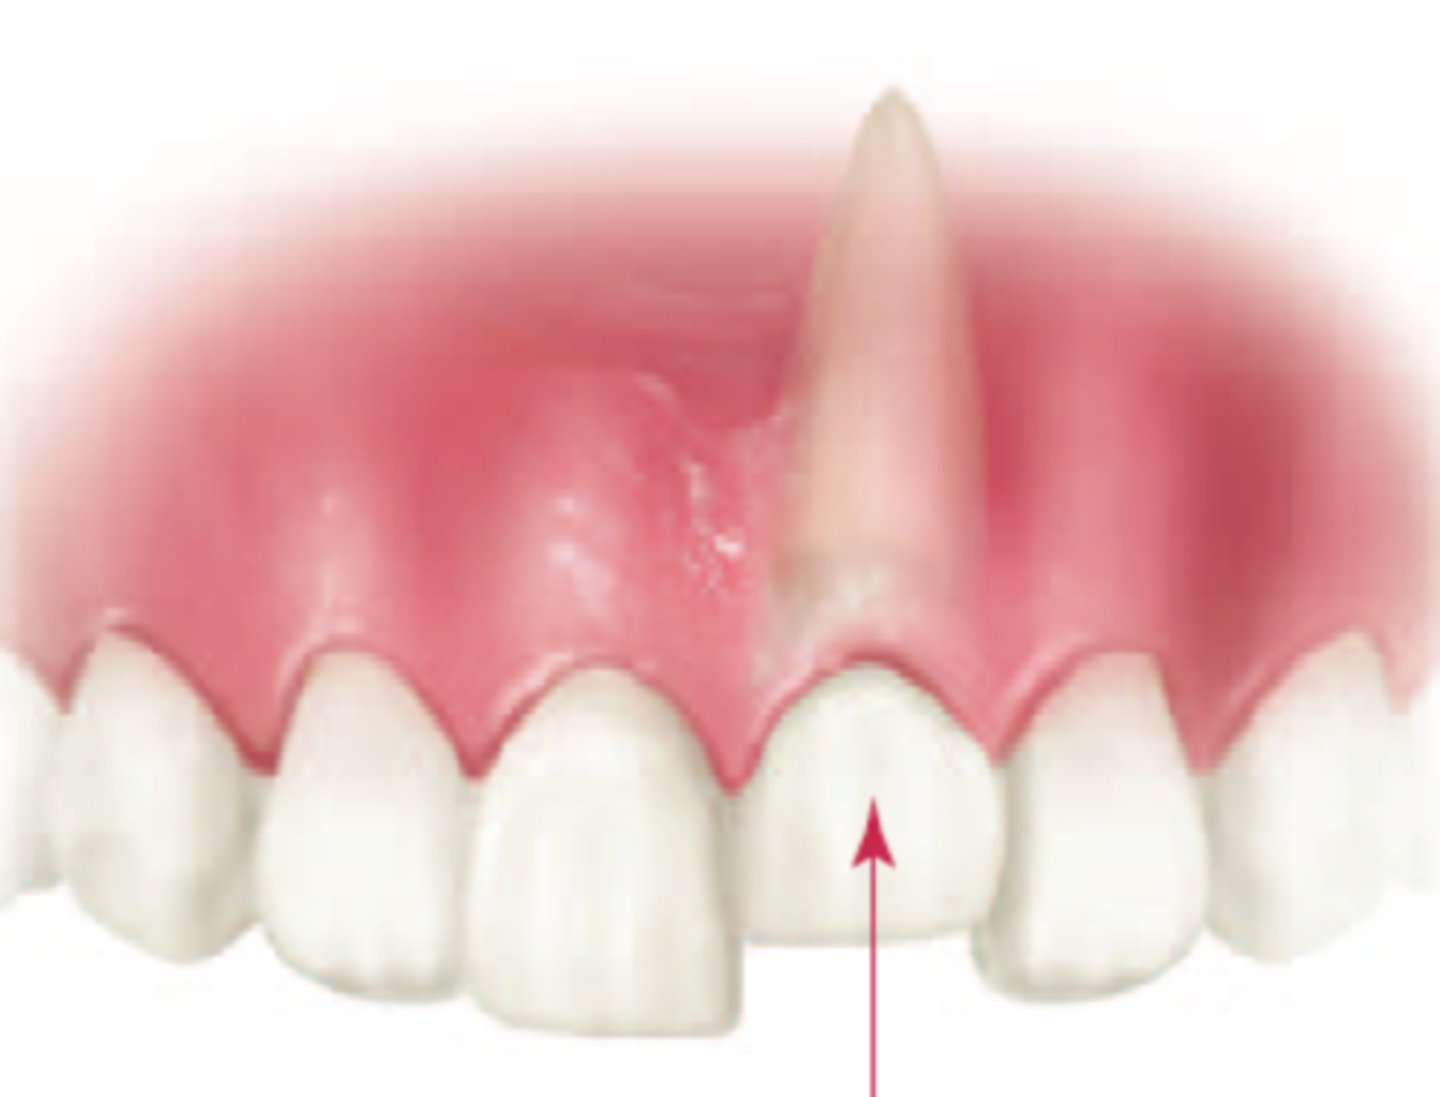

Extrusive Luxation

partial displacement of the tooth out the socket

If the tooth is excessively mobile > 3 mm, what is the treatment?

EXT